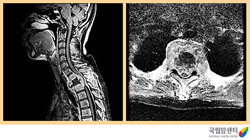

전이성 척수종양의 자기공명 영상촬영 소견

2009.08.21